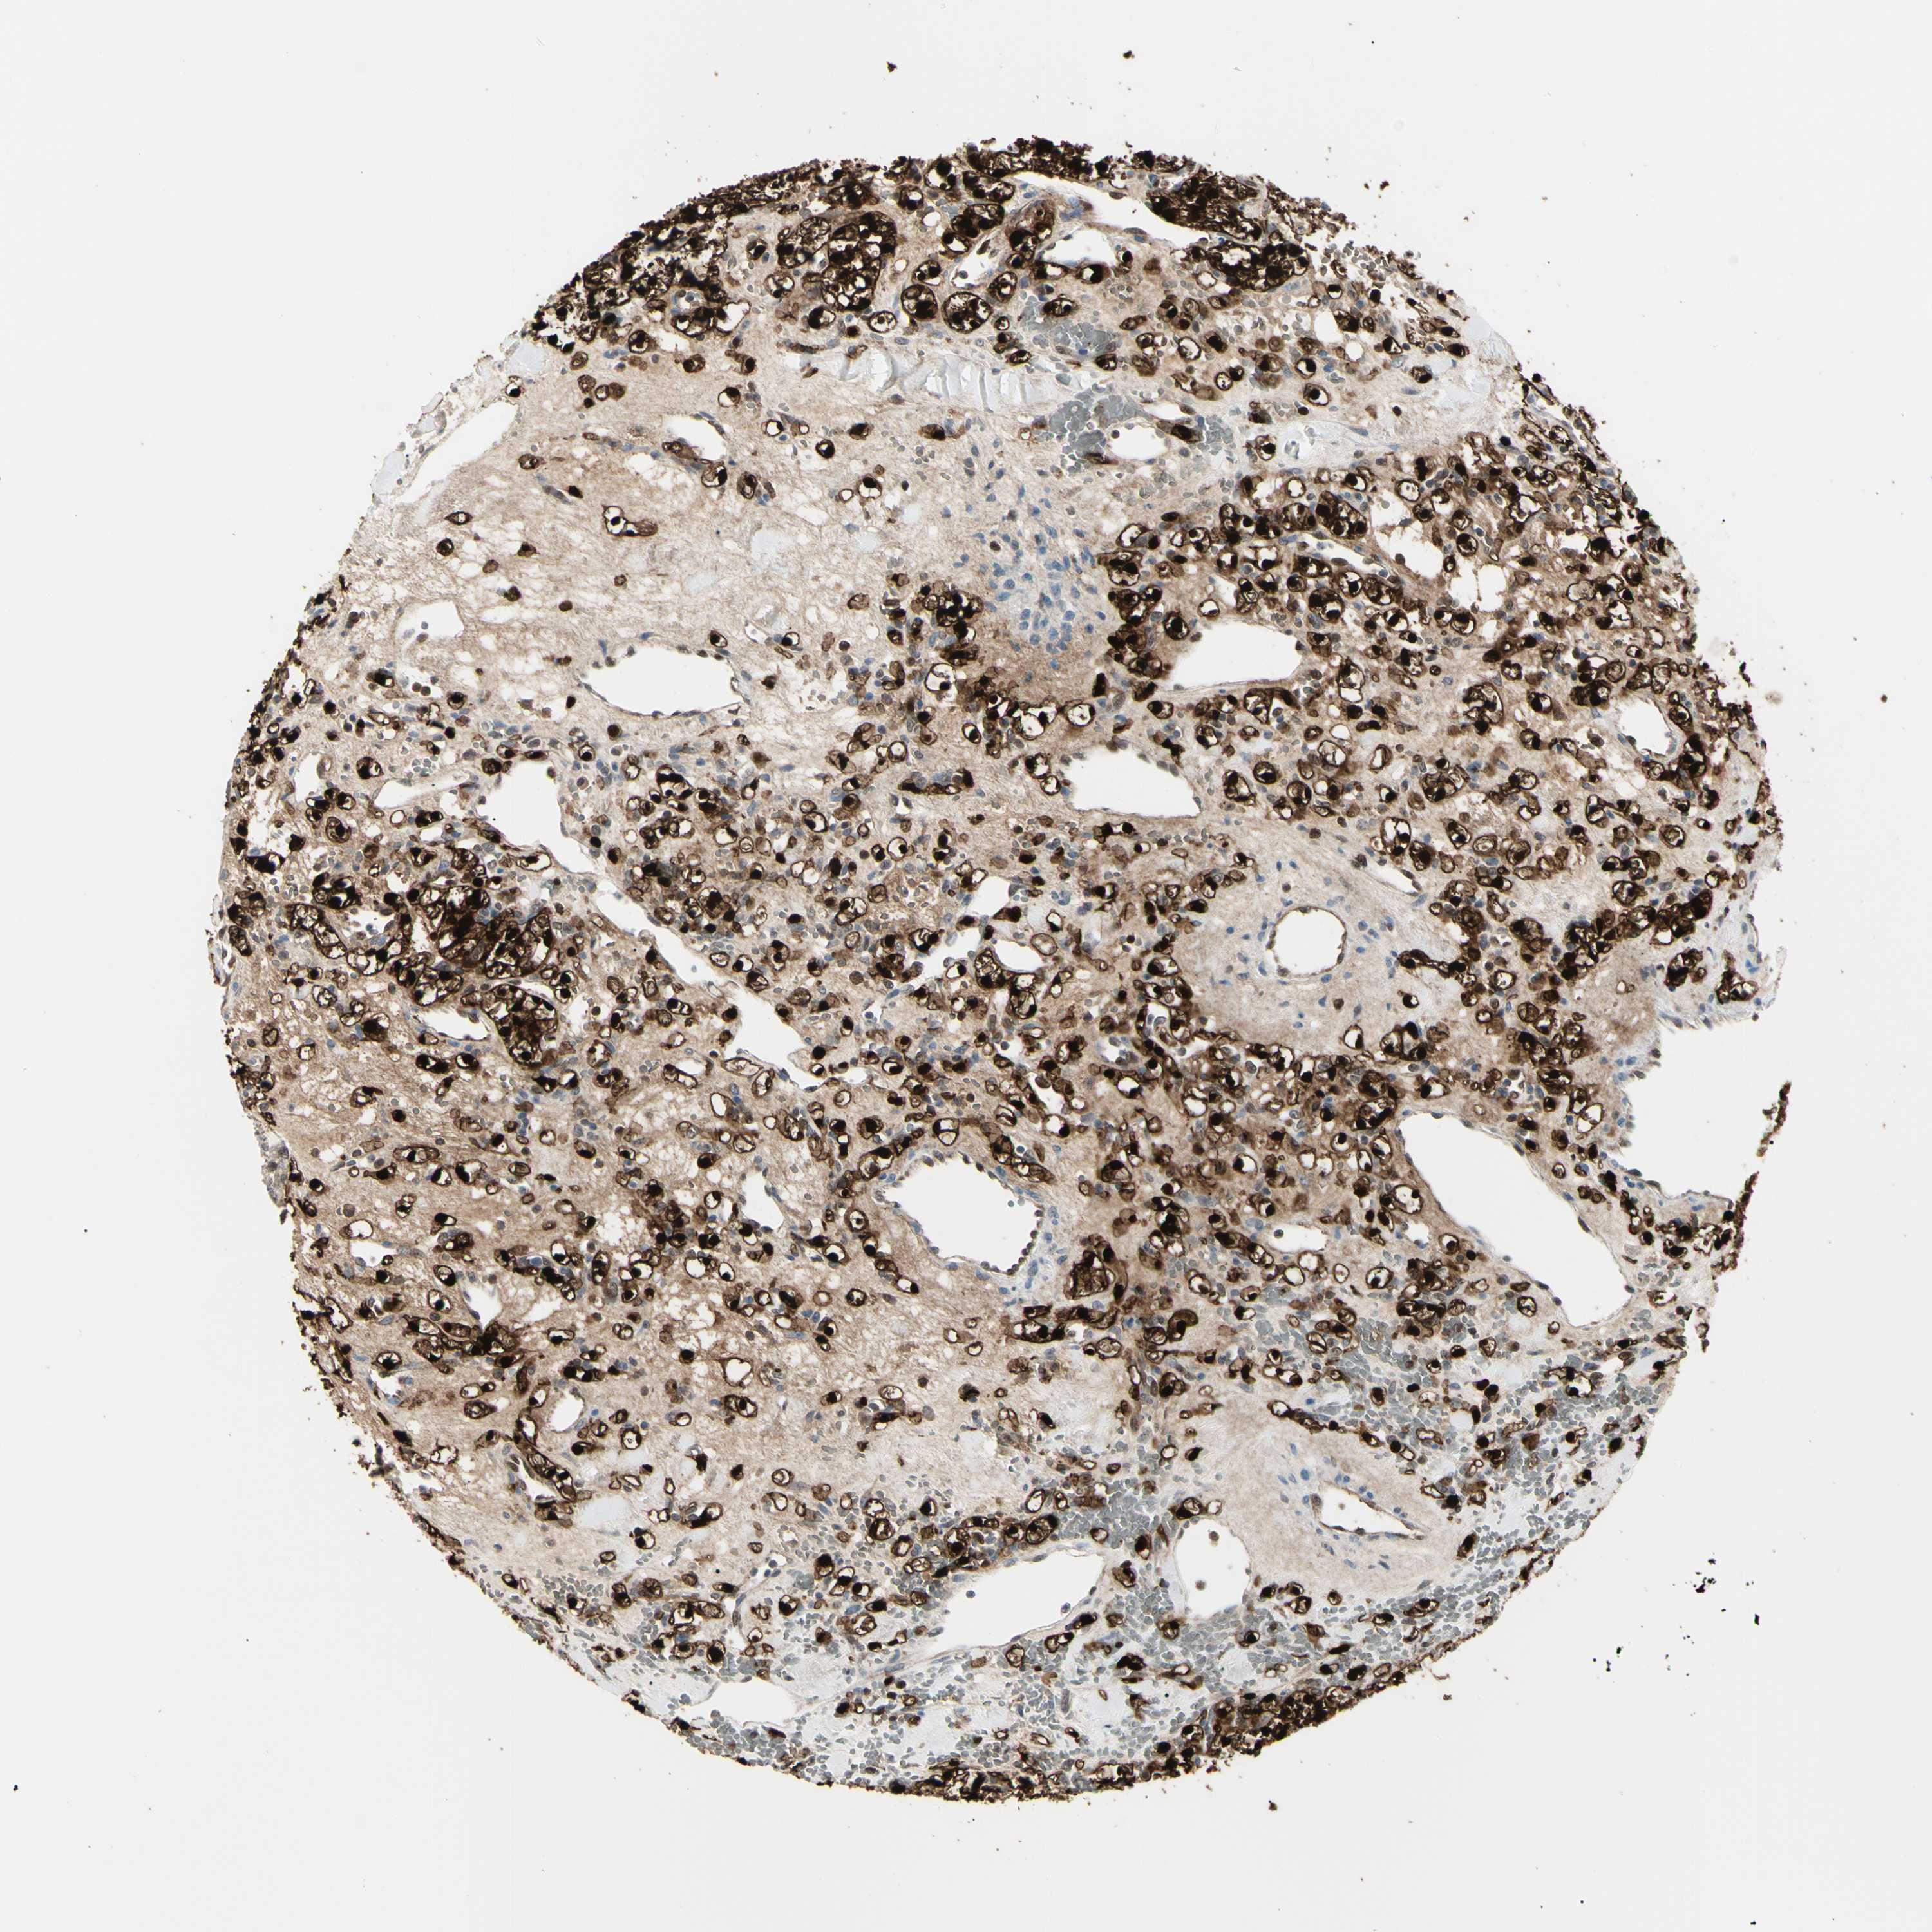

CANCER RENAL CANCER Show tissue menu

KICH TCGA KIRC TCGA KIRC VALIDATION KIRP TCGA PROTEIN RCC CPTAC PROTEIN EXPRESSION